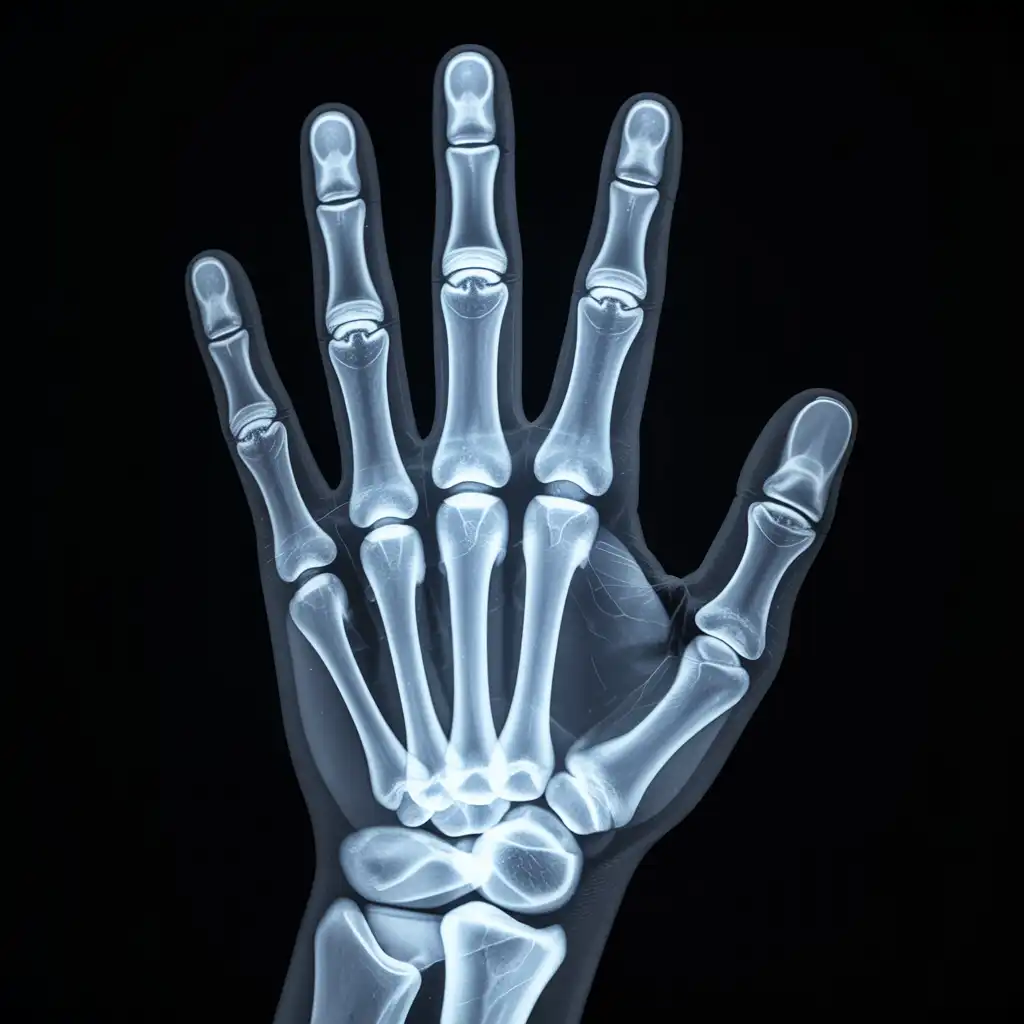

Da anni offriamo un servizio di radiografie a domicilio pensato per garantire ai nostri pazienti la stessa qualità diagnostica degli esami eseguiti in ospedale, ma con la comodità e la sicurezza della propria casa.

Abbiamo effettuato migliaia di esami direttamente presso abitazioni, residenze e strutture assistenziali, utilizzando apparecchiature digitali portatili certificate e procedure rapide e sicure.